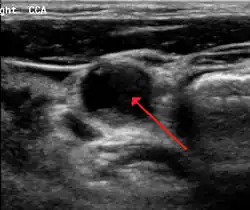

Carotid artery stenosis is usually diagnosed by color flow duplex ultrasound scan of the carotid arteries in the neck. This involves no radiation, no needles and no contrast agents that may cause allergic reactions. This test has good sensitivity and specificity.[16]

Typically duplex ultrasound scan is the only investigation required for decision making in carotid stenosis as it is widely available and rapidly performed. However, further imaging can be required if the stenosis is not near the bifurcation of the carotid artery.[17]